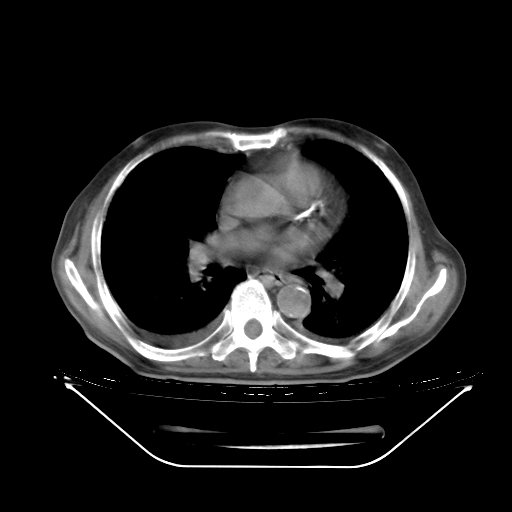

今天复查肺部CT,发现双肺广泛磨玻璃样改变。所以我把3月19日和5月9日相隔50天的肺部CT上传。请大家会诊。

5月9日肺部CT(在4月27日齐鲁医院肺部CT描述部分肺组织磨玻璃样改变,12天后肺组织广泛磨玻璃样改变)

2009年5月9日肺部CT

大致读了系列胸部CT:纵隔窗无明显异常,肺窗:从4、27至今:主要是双肺中下野外带可见毛玻璃样改变,目前处于急性肺泡炎阶段,至于原因考虑1、结替组织或胶原血管性疾病所致?2、恶性疾病如恶组在肺部所致的表现或细支气管肺泡癌?3、药物或其它原因如肺蛋白沉着症所致肺泡炎目前不太可能?总之,明天就去请我院的呼吸科、感染科、血液科和临免专家会诊哈。